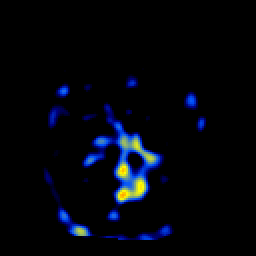

SPECT TL Study #1 -- Slice #31

[Home][Help][Clinical][Tour 1][Tour 2][Tour 3] Slice 31